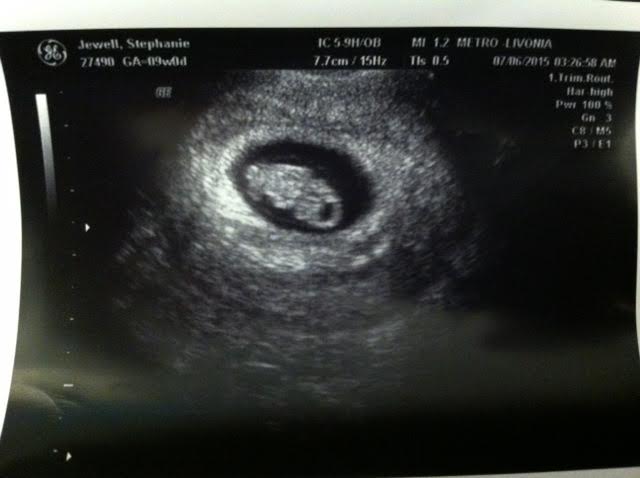

S/P L salpingo-oophorectomy w/ septic torsion 1999, dx moderate to severe Crohn's dz 2004. DH S/P hypospadic sx w/ multiple subsequent scar tissue removals, S/P herniorrhaphy. Married on 10/7/2006! TTC since May 2011; abnormal SA #1, better SA #2, normal HSG 7/2012, dx MFI/ low egg count, IUI!